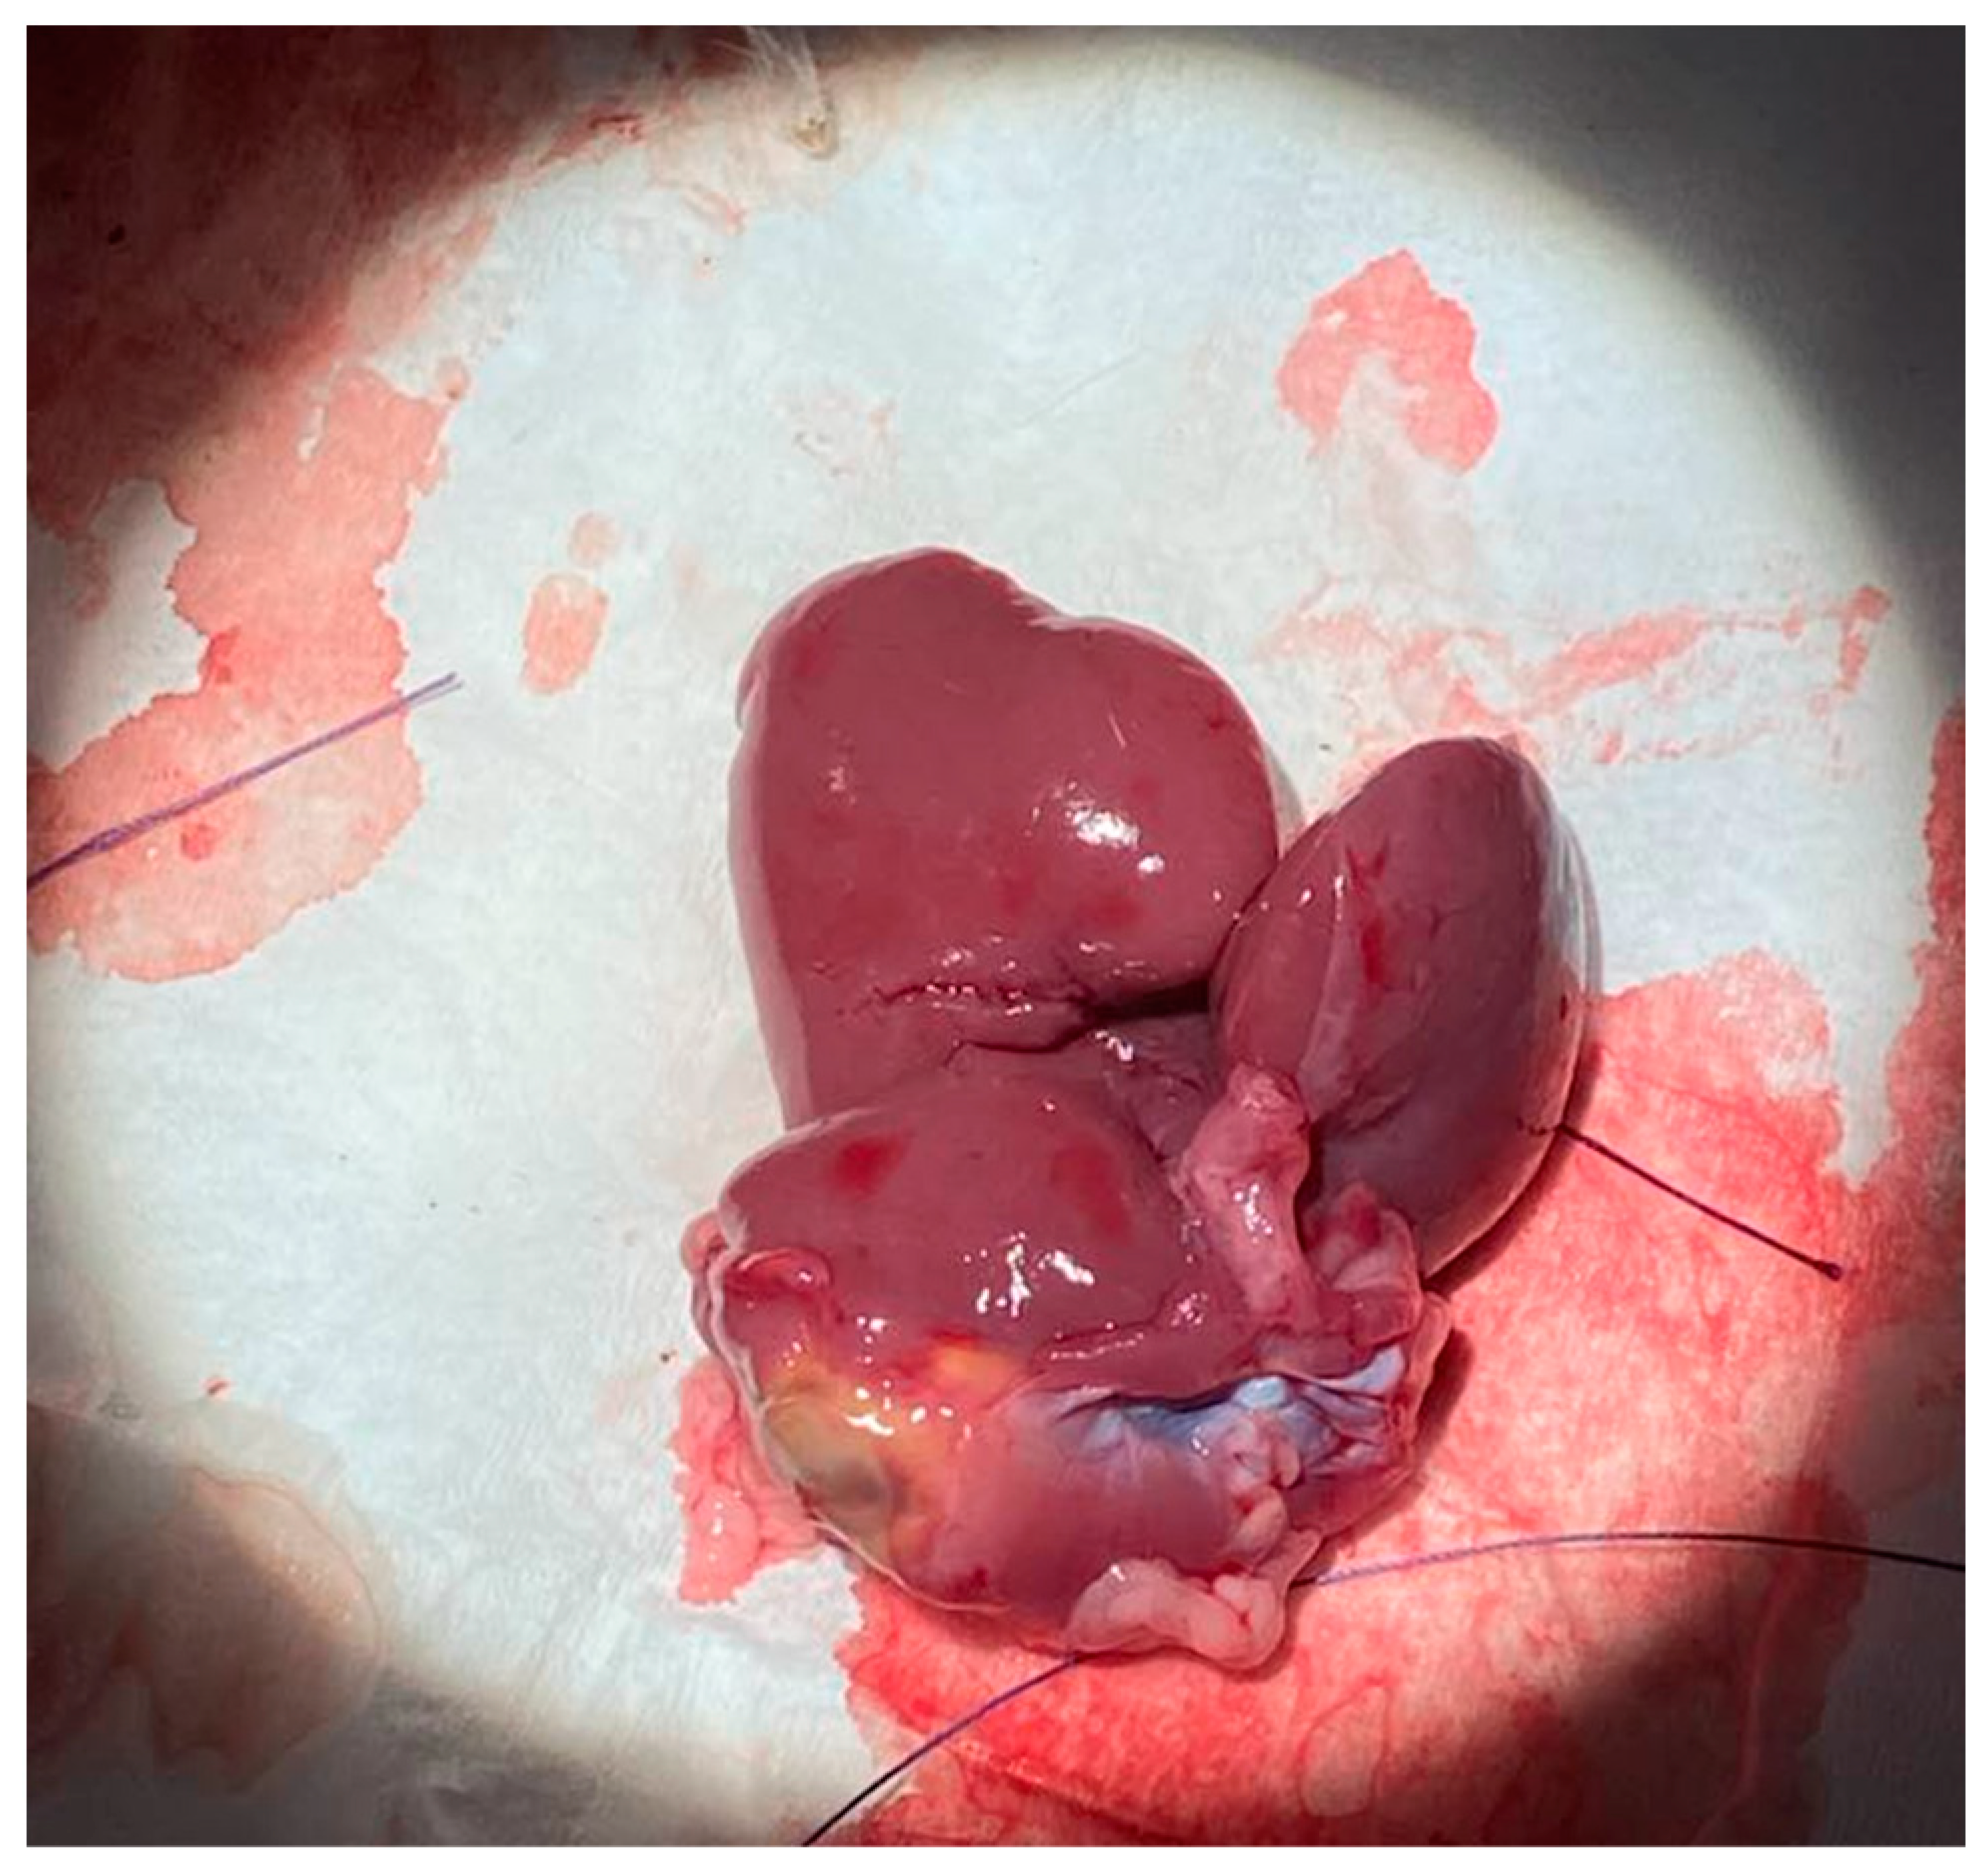

Five Sprague–Dawley male rats, sourced from Charles River laboratories, were used, all being between 300 g–400 g at the time of the operation. The mass of resected liver tissue was weighed and total liver mass was estimated using Equation (1) where mass of the resected liver (MR) is divided by 0.9 to estimate the total pre-surgical liver mass (MT). All five rats were monitored daily for the seven-day post-surgical period to adjust post-op care as necessary. Additionally, the mass of each rat was weighed for the first three days of the post-operative period. Following the seven-day period, all rats were euthanized and sacrificed for blood and liver samples. The total remaining liver was harvested and weighed. Figure 10 depicts the explanted liver after sacrifice on postoperative day 7.

Figure 10. Explanted Inferior and Superior Caudate Lobe after sacrifice on postoperative day 7.